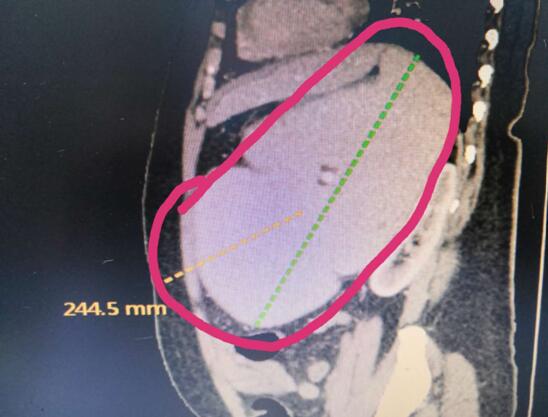

患者B,女,51歲,因牙齦出血1年入院,入院診斷為:乙肝,肝炎后肝硬化,門脈高壓癥,巨脾,脾亢,白細胞、血小板減少,中度貧血。5年前,曾在外院行介入脾栓塞術(shù),脾臟不僅沒有縮小,反而越來越大,脾下緣已經(jīng)超過腹部正中線、抵達臍部,就像幾個月“身孕”的婦女,給病人帶來巨大身心負擔(dān)。

(術(shù)前腹部CT顯示巨脾)